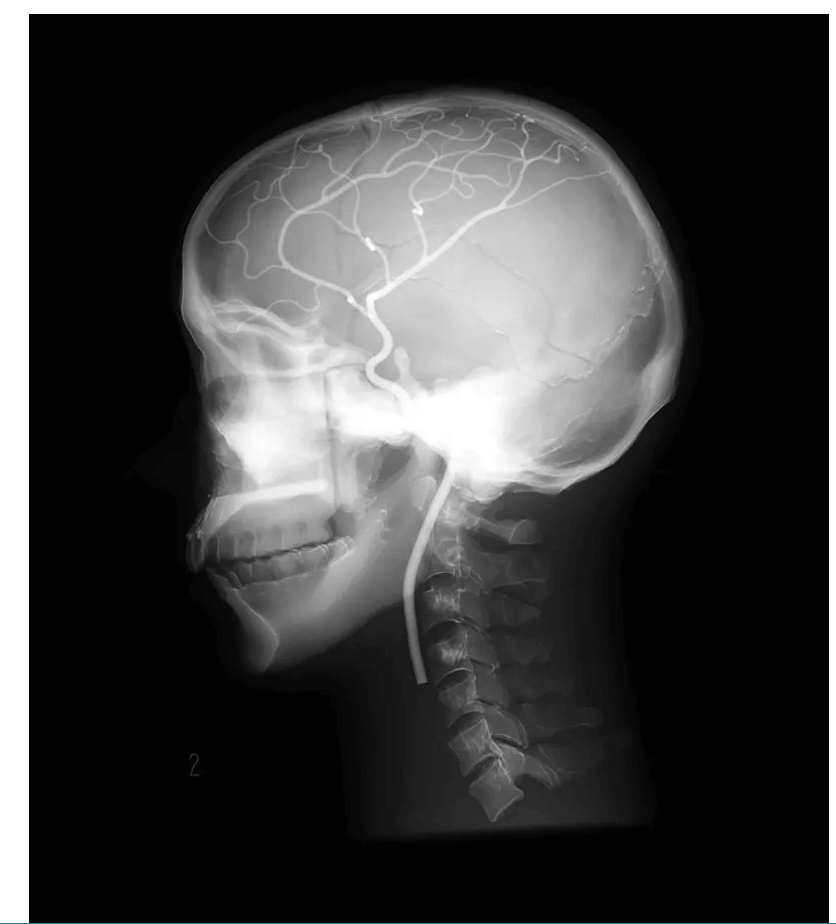

Das Angiographie Kopfmodell ist ein hochpräzises Trainingsmodell, das einen synthetischen Schädel in einen Kunststoffkopf integriert. In der linken Schädelhälfte sind die vordere und mittlere Hirnarterie nachgebildet und mit Kontrastmittel gefüllt, um realistische Trainingsbedingungen für die Angiographie zu schaffen. Die simulierten Arterien haben einen Durchmesser von 0,5 mm bis 4 mm und ermöglichen so eine detaillierte Untersuchung und Diagnose von Gefäßstrukturen im Gehirn. Dieses Modell ist besonders geeignet für medizinische Fachkräfte, die ihre Fähigkeiten in der Angiographie und Bildgebung von Gehirngefäßen verbessern möchten.

Präzise Nachbildung der vorderen und mittleren Hirnarterien im synthetischen Schädel

Arterien mit Durchmessern von 0,5 mm bis 4 mm für detaillierte Bildgebungstraining

Mit Kontrastmittel gefüllte Arterien ermöglichen realistische Angiographie-Simulationen